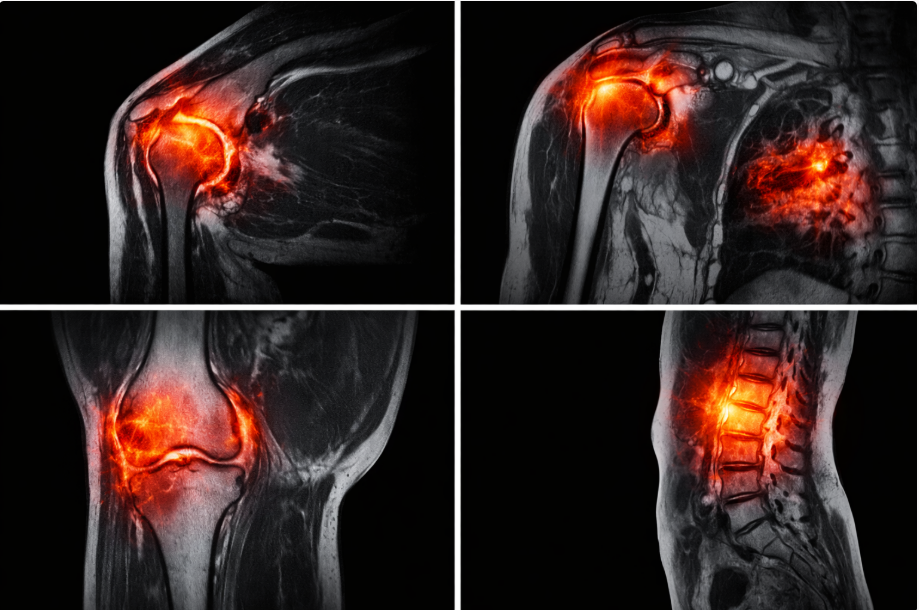

.

Progression of chronic synovial inflammation and cartilage degradation caused by sustained cytokine signaling.

(Source: MRI-based musculoskeletal inflammation studies, Journal of Rheumatology, 2024)